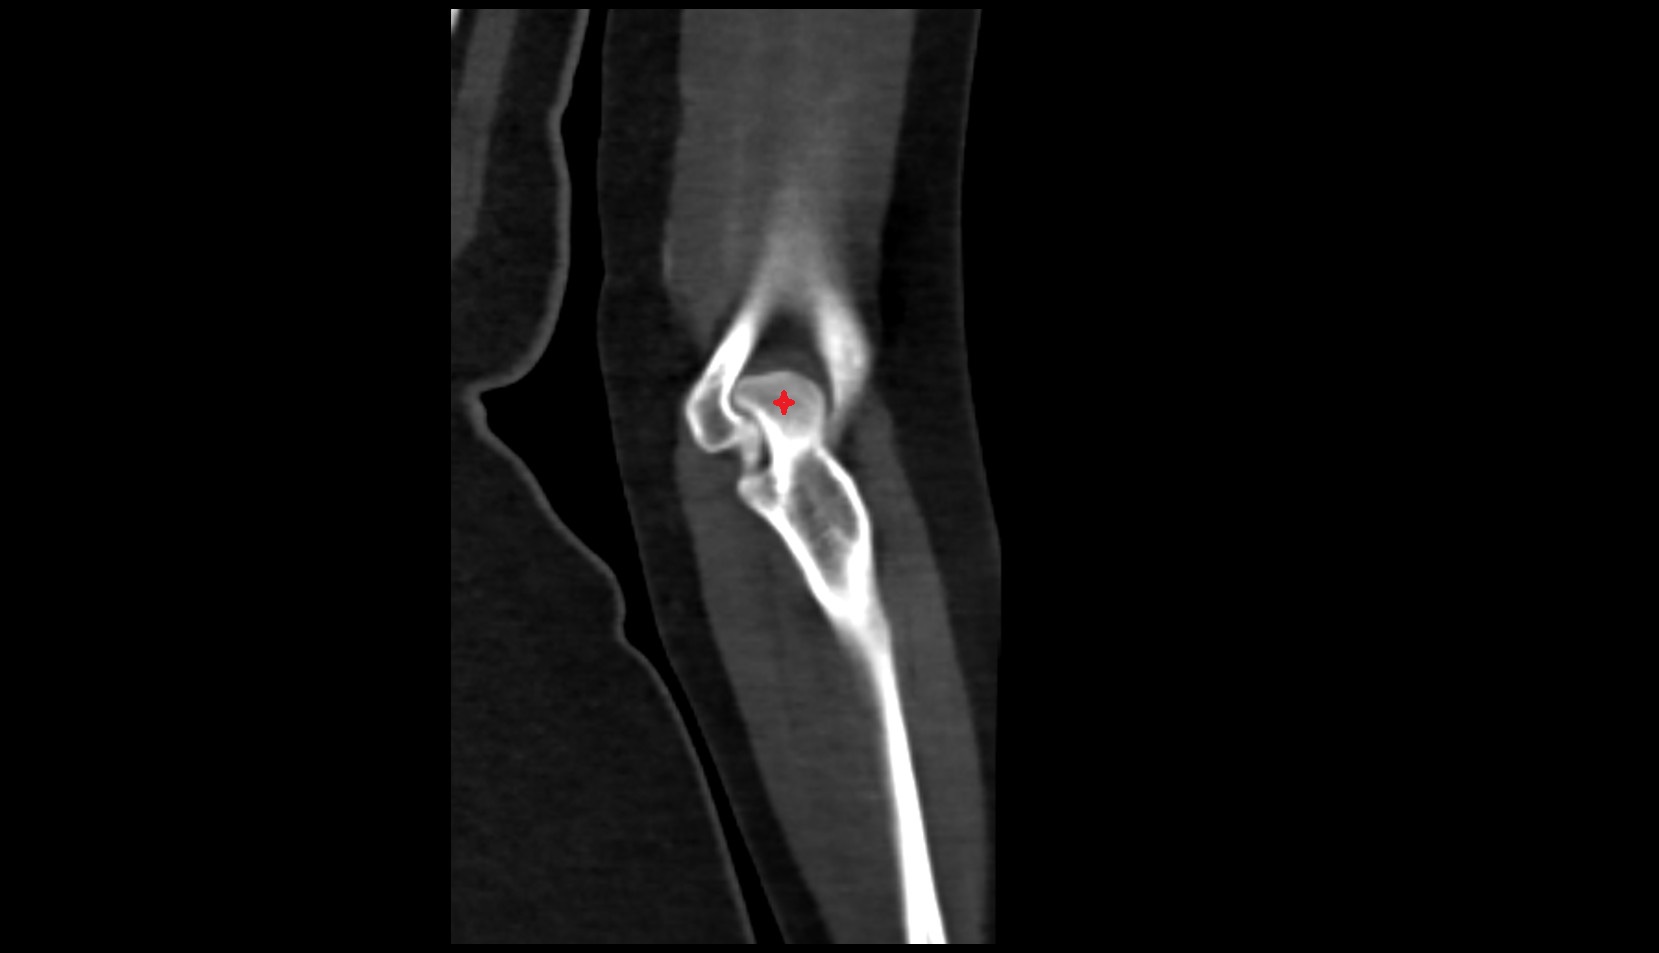

- Elbow joint

- Olecranon

- Coronoid process of ulna

- Capitulum of humerus

- Trochlea of humerus

- Head of radius

- Neck of radius

- Trochlear notch of ulna

- Coronoid fossa

- Humeroulnar joint

- Humeroradial joint

- Proximal radioulnar joint